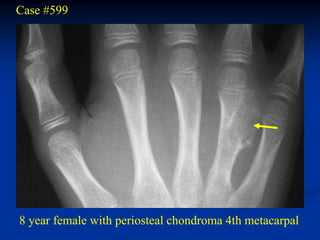

Case #599

8 year female with periosteal chondroma 4th metacarpal